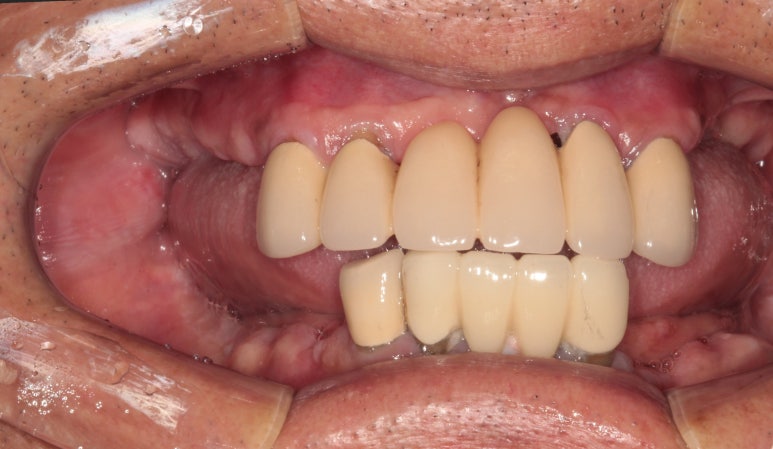

좌측 어금니 또한 깔끔하게 그럴싸하게!! 본인치아와 흡사한 형태로 제작해드렸습니다.

사실 처음에 잇몸 염증으로 고름이 가득 차있던 왼쪽 아래 송곳니 부위에는 임플란트 심는 것 자체가 불가능 했습니다만, 인접한 자리에 임플란트를 심어내어 마치 임플란트가 있는 것 같이 깔끔하게 제작 완료!

위턱 교합면에서도,

아래턱 교합면에서도 아주 정갈하고 깔끔하게 임플란트 크라운이 잘 제작된 것을 보실 수 있습니다.

사실 어디하나 흠잡을데 없다고 생각합니다....호호...